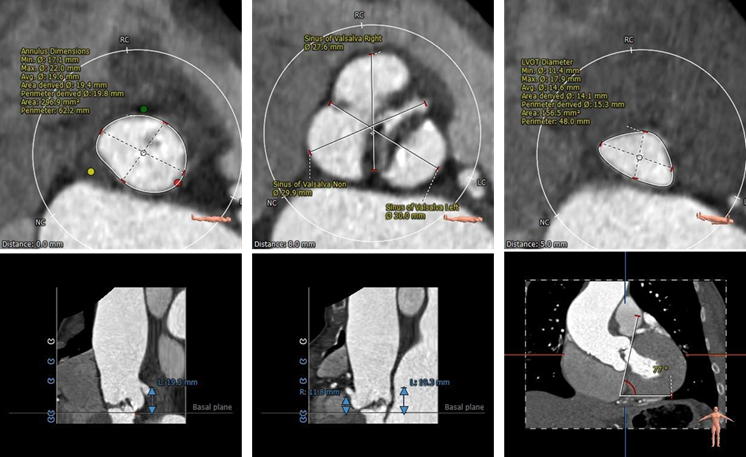

术前CT检查及评估

主动脉根部评估

Type1型二叶瓣,右无冠窦发育不全,交界处形成非钙化嵴,伴有瓣叶严重纤维增厚。

右冠高度11.8mm,左冠高度19.3mm,双侧瓣叶长度小于瓣叶附着缘到冠脉开口距离,冠脉遮挡风险较小。

主动脉瓣环与水平面夹角77°,呈横位心。

瓣环上解剖评估

瓣环上轻度钙化,瓣叶纤维增厚明显,瓣上最狭窄处周长:59.5mm,直径:18.8mm。

左心室解剖评估

左心室腔小、心肌肥厚,术中超硬导丝、球囊、瓣膜胶囊腔的压迫下均有可能出现急性大量主动脉瓣反流而导致低血压甚至循环崩溃的风险。